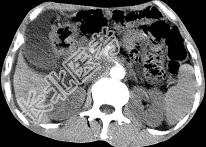

- 单项选择题女,50岁, 中上腹疼痛,消瘦乏力, 影像检查如下图,最佳的诊断是  (    )

- A、慢性胰腺炎

- B、急性胰腺炎

- C、胰腺癌并腹膜后淋巴结转移

- D、胰岛素瘤

- E、腹膜后淋巴瘤